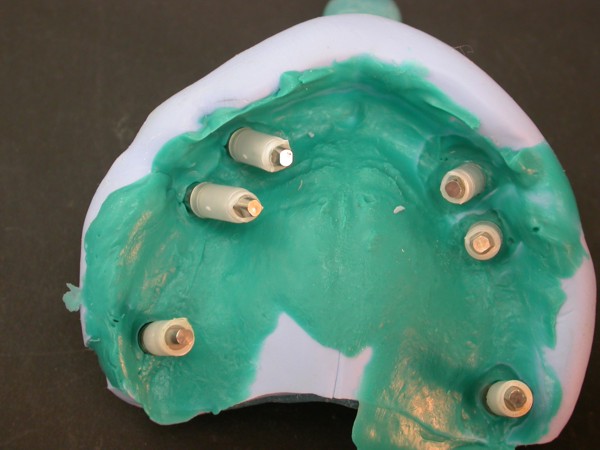

ABSTRACT La literatura oclusal se ha encargado de describir distintas funciones de la misma a través de los tiempos. El presente caso se realiza en forma de sobredentadura (over denture) debido a que la carencia de reborde óseo en el sector anterior verificado tanto clínicamente como mediante telerradiografía , impedía llevar a cabo una prótesis fija , por lo que se optó por un sistema de pilares ceramizados y paralelizados mediante el sistema SIRIUS, sobre seis implantes, y la conexión a una estructura de metal cerámica FIJA AMOVIBLE, mediante coronas telescópicas galvanizadas, otorgando al sistema la rehabilitación mediante una PIA(Prótesis Implanto Asistida con reposición ósea y gingival mediante porcelana rosa.) MATERIAL Y MÉTODOS: IMPLANTES:KLOCKNER SK-T.T.S. MONTAJE Y REGISTROS: ARCO FACIAL ESTÁTICO Y ARTICULADOR PRIMARIA: Abuttmets Ceramizados (I.P.S. D.SIGN IVOCLAR) SECUNDARIA: Cofias Galvanoformadas (AURO GALVAN CROWN WIELAND) TERCIARIA: Férula de Porcelana sobre Metal (I.P.S. D. SIGN IVOCLAR) CEMENTADO INTERFASE: NIMETIC CEM-ESPE DESARROLLO Se presenta el paciente a la consulta requiriendo la resolución de su maxilar inferior, el que se restaura mediante una férula de metal porcelana , en la que se preparan los lineamientos oclusales ideales (Spee-Wilson-Cuatro Niveles-etc) a fin de tener un sustrato de trabajo correcto, para la confección del maxilar superior, que porta una Prótesis Total convencional. Se estudia mediante Panorámica, Dentascan y Montaje en articulador semi ajustable. Se instalan seis implantes Klockner con Técnica Semisumergida pensados para una Carga diferida a tres meses después de la implantación Se realiza el arrastre de los Transfer mediante cubeta individualizada y fenestrada. Se confeccionan los abuttmentes correspondientes y se llevan a boca mediante una férula de posicionamiento realizada en Acrílico Duralay, el que por sus condiciones de carencia de cambios volumétricos verifican el correcto ajuste de los mismos Se ceramizan los abuttments y se paralelizan mediante el sistema SIRIUS, llevándolos a boca y chequeando su instalación Se confecciona una Prótesis Total Provisional que llevará el paciente durante el período de Osteointegración Se procede a la confección en laboratorio de las cofias galvánicas Sobre un nuevo modelo mayor se confecciona la férula de metal que uniremos en boca a las cofias galvanizadas mediante un cemento especial, una vez confeccionada la porcelana. Se prueba en boca la férula metálica, verificando su holgura que será ocupada por el cemento antedicho, y se comienza con el montaje de la cerámica y la verificación de los patrones oclusales de la misma. Se instala el todo haciendo morder al paciente con el medio cementante instalado. FIGURA 40 FIGURA 41 FIGURA 42 CONCLUSIONES La función de «GUIA CANINA», como esquema mas propicio para cumplir con los deseos de «autoprotección » de un SEG, rehabilitado o no, no se cumple al 100 % en casos como el presentado. La razones por las cuales el uso de la misma en lo que se da en denominar OCLUSIÓN MUTUAMENTE PROTEGIDA consiste en tres factores que detallo a continuación: A. En una función desoclusiva realizada por las piezas anteriores, como por ejemplo el canino, el BRAZO DE RESISTENCIA generado en la palanca desoclusiva, es por lo menos igual al brazo de potencia desarrollado, argumento de gran peso para hablar de la Desoclusión Canina como esquema de elección- B. La inclinación de los rebordes marginales del canino superior, esta dentro de los 70º, a diferencia de la tabla oclusal posterior que puede variar entre los 20 y 40 º. C. El estimulo que generan los dientes anteriores se dirige por via aferente al SNC, exitando por vía eferente, fundamentalmente al músculo temporal en sus fibras anteriores o VERTICALES…fibras de mucha menos capacidad de fuerza, que si la acción la ejercieran las fibras de la cincha PTERIGO MASETERINA, que serían exitadas en el caso de una Función de Grupo. EN EL CASO PRESENTADO LAS DOS PRIMERAS RAZONES TIENEN VIGENCIA. Sin embargo la última de ellas , al no tener los Implantes terminaciones nerviosas como las que posee el periodonto , los estímulos que llegan al SNC no se cumplen, y por lo tanto no existe la respuesta que por conducción eferente estimularía al músculo temporal a su acción. De la misma manera, el hecho que estos Implantes estén ferulizados , trasmite fuerzas laterales también a los posteriores, y no solo a los que actúan como caninos. El beneficio de las dos primeras razones de uso de una Función Canina en un caso como este, obedece a que de por si las mismas minimizan la acción direccional de las fuerzas, las que sin embargo son compartidas por las piezas posteriores tanto del LT como del LnT. En este compartir de la función, me resulta conveniente denominar a este esquema: FUNCIÓN DE GRUPO POSTERIOR DE ACCIÓN CANINA. ———————————————————————————————————- PIE DE FOTOS: 37: CASO TERMINADO